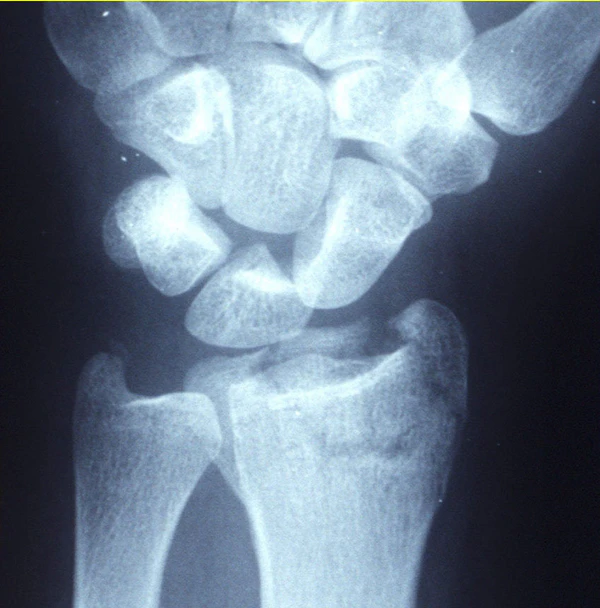

Диагноз может быть очевиден клинически при деформации дистального отдела лучевой кости, но должен быть подтверждён рентгенологическим исследованием. В некоторых случаях переломы могут быть не видны на рентгеновских снимках сразу после травмы. Подтвердить диагноз можно с помощью отсроченной рентгенографии, компьютерной томографии (КТ) или магнитно-резонансной томографии (МРТ)[1].

Для точного подтверждения диагноза всем пациентам с подозрением на перелом дистального отдела лучевой кости следует провести рентгенографию лучезапястного сустава в как минимум двух проекциях. Если результаты рентгенографии недостаточны для оценки состояния, рекомендуется выполнить компьютерную томографию (КТ) суставов. Этот метод помогает уточнить диагноз и планировать хирургическое лечение при переломах[2].